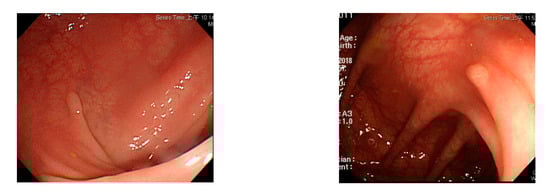

Figure 2.

Excessive intestinal wall textures with small polyps.

Currently, many medical images are processed into grayscale images, such as ultrasound, computed tomography (CT), and magnetic resonance (MR) images. Tan et al. [44] applied a gray-level cooccurrence matrix and CNN to CT images for polyp diagnosis. Zhang et al. [45] compress the three-channel color images of chest CT to grayscale images. A five-layer deep CNN with stochastic pooling is used to diagnose chest-based COVID-19. Xie et al. [46] mentioned that in deep learning, colors are not the key features influencing accurate image classification. They also discovered that in X-ray image classification, the speed and accuracy of processing grayscale images were considerably higher than those of processing RGB images. The grayscale method used was ITU-R Recommendation BT.601 [47]. Moreover, misjudgments were easily made in the presence of excessive intestinal wall textures, when polyps were too small (Figure 2), and when polyp textures were similar (Figure 3) to intestinal wall textures.